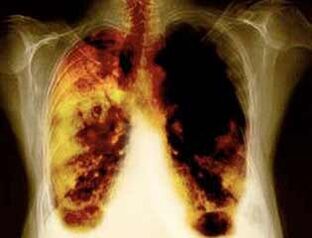

- Biriketako minbizia eta beste minbizi mota asko garatzeko arriskua murriztea.

- Biriketako gaixotasun batzuk garatzeko arriskua murriztea (adibidez, biriketako gaixotasun oztopatzaile kronikoa).

- % 40 erretzea utzi ondoren 10 urte, biriketako minbiziaren probabilitatea% 40 murrizten da.